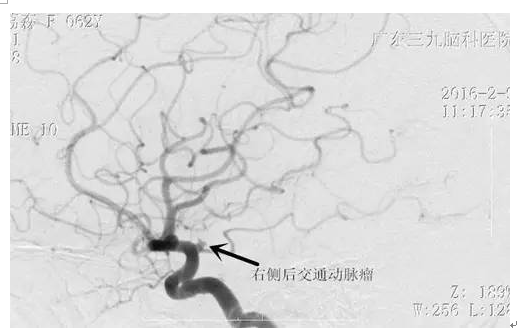

周阿姨,63岁,突发性头痛20小时,就诊当地医院CT示:蛛网膜下腔出血。为求进一步治疗,来我院就诊。入院后完善相关检查,检查提示:右侧后交通动脉瘤,左侧颈内动脉动脉瘤,行介入栓塞治疗去除动脉瘤。病人经系统治疗后颅内血肿完全吸收,头痛缓解,康复出院。